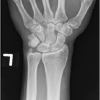

A 26-year-old right-hand dominant Caucasian male without significant medical history landed on his outstretched left hand when crashing his all-terrain vehicle, resulting in immediate pain and swelling. An outside urgent care center found no fractures or dislocations on plain radiographs and subsequently splinted the left wrist due to pain. He presented to an orthopedic hand surgery outpatient office 4 weeks after the injury with persistent pain and decreased range of motion. No obvious deformity was noted, but the patient was tender to palpation over the dorsal carpus as well as the carpal tunnel. The patient was neurovascularly intact at the time of presentation. New plain radiographs were obtained, demonstrating an isolated dorsal hamate dislocation in the absence of any fracture, as noted in Fig. 1 and 2. Given the chronicity of the injury, closed reduction was not attempted due to the high likelihood of failure. The patient underwent an open reduction with internal fixation of the isolated hamate dislocation.